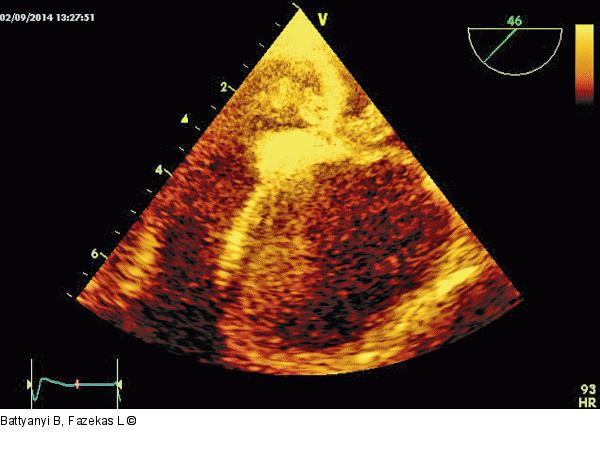

Abbildung 3: Thromboemolus Der "fixierte" Teil des Thromboembolus mit dem Durchschnitt vom rechten in den linken Vorhof. |

Der "fixierte" Teil des Thromboembolus mit dem Durchschnitt vom rechten in den linken Vorhof. |